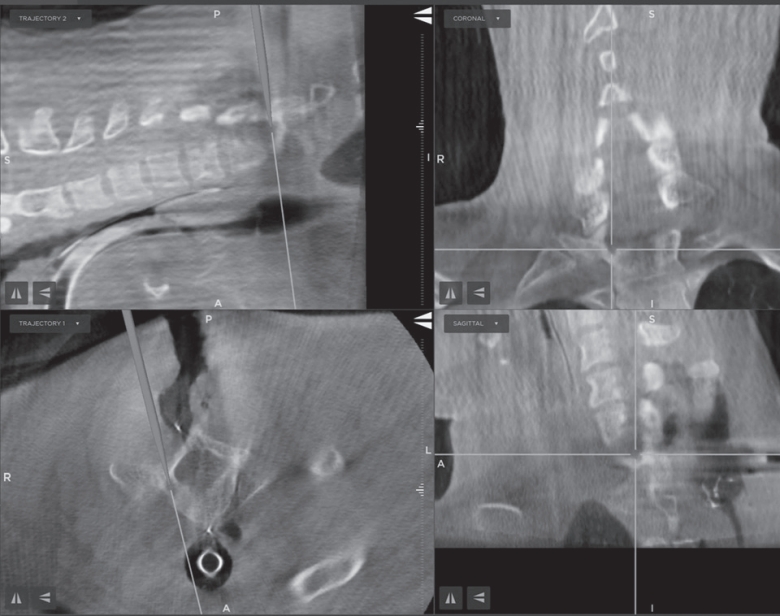

TM navigation platform (Medtronic Inc., USA). The lesion was accurately localized at the junction between the superior pedicular cortex and the transverse process of T1, just inferior to the transverse foramen (

Fig. 2). Using the navigation pointer, the surgical entry point was planned to avoid disruption of the vertebral artery and facet complex. A high-speed diamond burr was used under microscopic magnification to perform a cortical window. The nidus was identified as a red-brown, well-circumscribed lesion with minimal surrounding bleeding. Complete en bloc resection of the nidus was achieved using curettes and a Kerrison punch. Care was taken to avoid injury to the transverse foramen, and no neural structures were exposed or manipulated during the procedure. Histopathological examination of the excised specimen revealed a well-vascularized nidus composed of woven bone trabeculae rimmed by active osteoblasts, consistent with osteoid osteoma. There was no evidence of malignancy. The patient experienced complete resolution of pain on the first postoperative night. No neurological complications occurred. He was mobilized without restriction on postoperative day 1 and discharged on day 2. At 6-week follow-up, he remained pain-free, had resumed full physical activity, and reported significant improvement in sleep quality. At the 6-month follow-up, repeat MRI and CT showed no evidence of recurrence or residual lesion (

Fig. 2.Intraoperative O-arm–based navigation image demonstrating real-time localization of the nidus during surgery. The navigation pointer is positioned over the superior cortex of the right T1 pedicle.